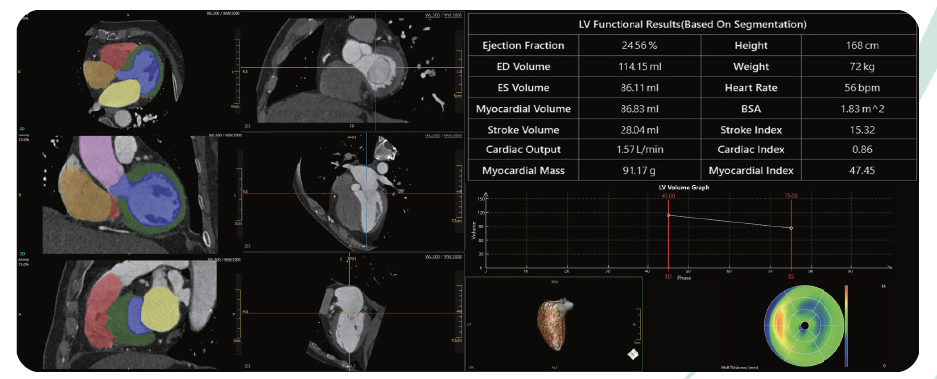

Soluții de Aplicație Post-procesare

NeuViz 64 In este proiectat pentru a oferi soluții cardiace care includ scorul de calciu cardiac, analiza funcției cardiace și chiar analiza coronariană. Oferă certitudine diagnostică completă pentru imagistica cardiacă.

Analiza Funcției Cardiace